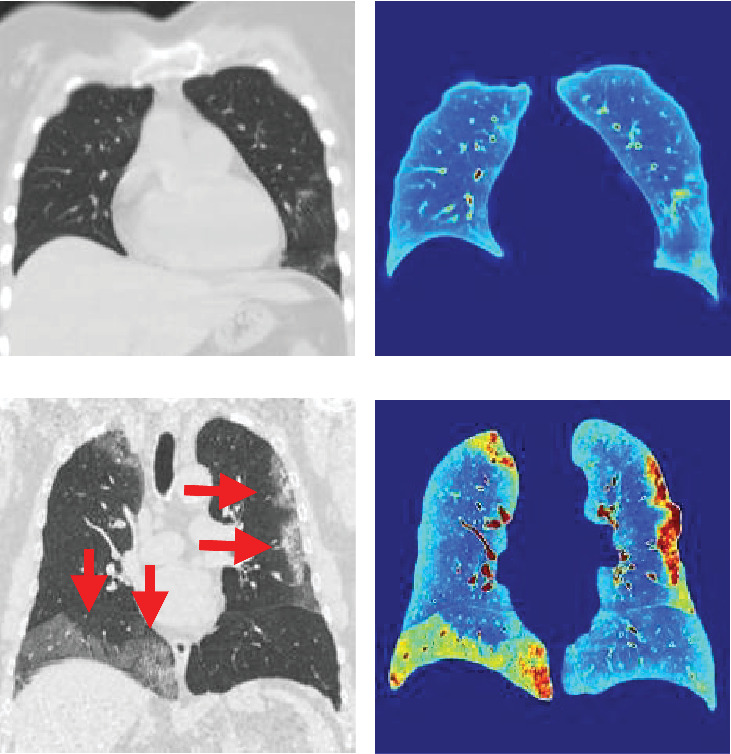

This study proposes an automated system for assessing lung damage severity in coronavirus disease 2019 (COVID-19) patients using computed tomography (CT) images. These preprocessed CT images identify the extent of pulmonary parenchyma (PP) and ground-glass opacity and pulmonary infiltrates (GGO-PIs). Two types of images-saliency (Q) image and discrete cosine transform (DCT) energy image-were generated from these images. A final fused (FF) image combining Q and DCT of PP and GGO-PI images was then obtained. Five convolutional neural networks (CNNs) and five classic classification techniques, trained using FF and grayscale PP images, were tested. Our study is aimed at showing that a CNN model, with preprocessed images as input, has significant advantages over grayscale images. Previous work in this field primarily focused on grayscale images, which presented some limitations. This paper demonstrates how optimal results can be obtained by using the FF image rather than just the grayscale PP image. As a result, CNN models outperformed traditional artificial intelligence classification techniques. Of these, Vgg16Net performed best, delivering top-tier classification results for COVID-19 severity assessment, with a recall rate of 95.38%, precision of 96%, accuracy of 95.84%, and area under the receiver operating characteristic (AUROC) curve of 0.9585; in addition, the Vgg16Net delivers the lowest false negative (FN) results. The dataset, comprising 44 COVID-19 patients, was split equally, with half used for training and half for testing.

Abstract Image